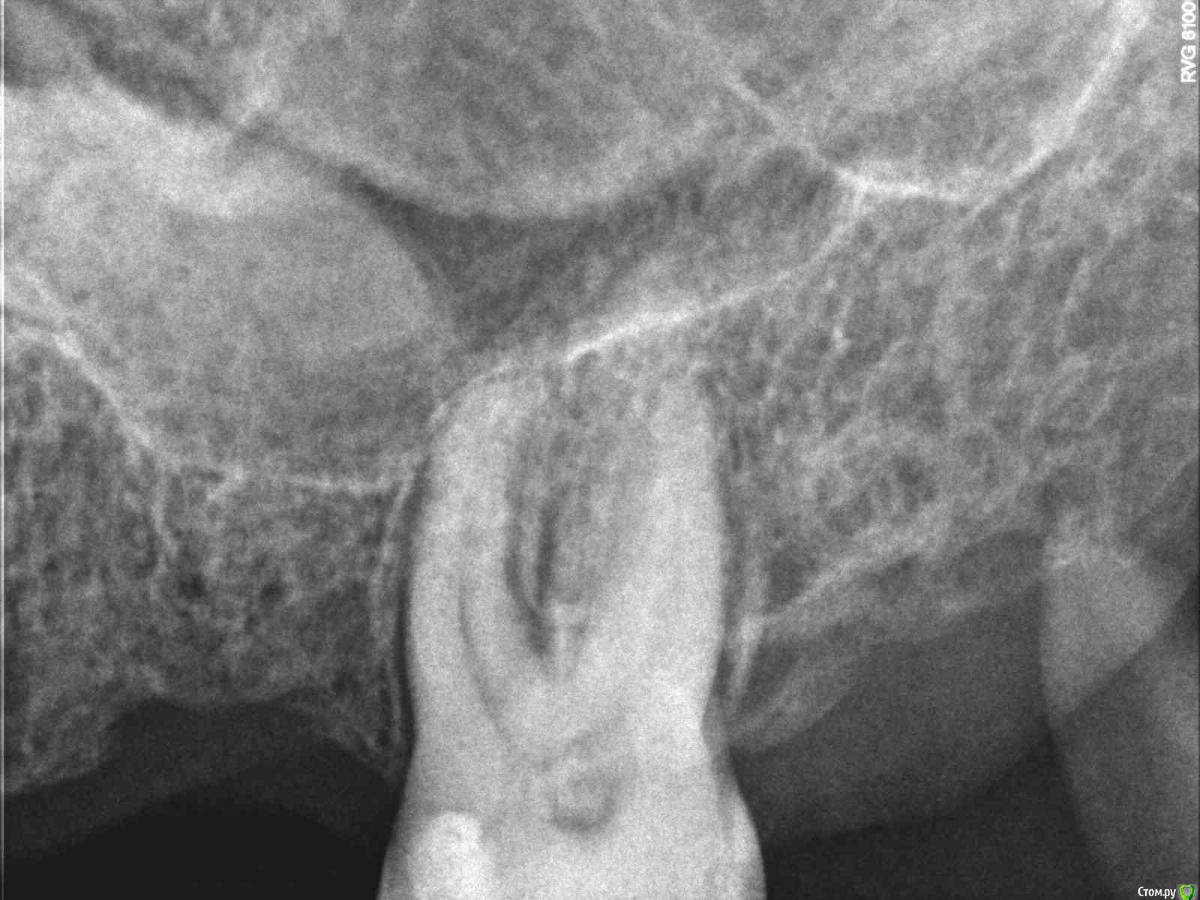

dsfksdkf Опубликовано 12 августа, 2015 Автор Поделиться Опубликовано 12 августа, 2015 (изменено) Вот в этом месте болит - черное в кости это что? С другой стороны по другому Изменено 12 августа, 2015 пользователем dsfksdkf Ссылка на комментарий

dsfksdkf Опубликовано 12 августа, 2015 Автор Поделиться Опубликовано 12 августа, 2015 Рассматривая фото я вдруг понял - связок в этом месте (белого) почти нет - хотя с другой стороны есть Ссылка на комментарий

St. Опубликовано 12 августа, 2015 Поделиться Опубликовано 12 августа, 2015 Связки вокруг зуба на таком снимке в принципе не видны. То что Вы имеете ввиду скорее всего структура кости. Ссылка на комментарий

Гарриевич Опубликовано 13 августа, 2015 Поделиться Опубликовано 13 августа, 2015 То, что Вы обвели в кружок выглядит устрашающе только изза большой контрастности. Сколько это зуб стоит так одиноко? Ссылка на комментарий